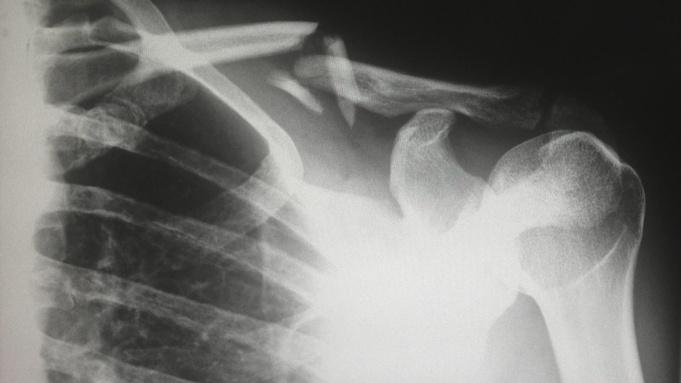

Что делать при сильном ушибе или переломе?

При ушибе или переломе без смещения нужно приложить холод, доступными средствами попытаться поменьше двигаться, обратиться, если это нужно, в травмпункт или поликлинику в дежурный день.

А вот если это вывих или перелом со смещением, то обязательно вызывайте скорую или обращайтесь в травмпункт (ближайший по месту жительства). Попытайтесь обездвижить травмированное место.

Не рекомендуется пытаться вправлять самому, прогревать или "вообще ничего не делать" более трех дней.